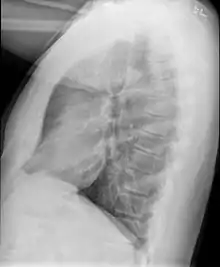

| Bronchiolitis obliterans[1] | |

| High resolution CT scan showing bronchiolitis obliterans with mosaic attenuation, bronchiectasis, air trapping and bronchial thickening[3] | |